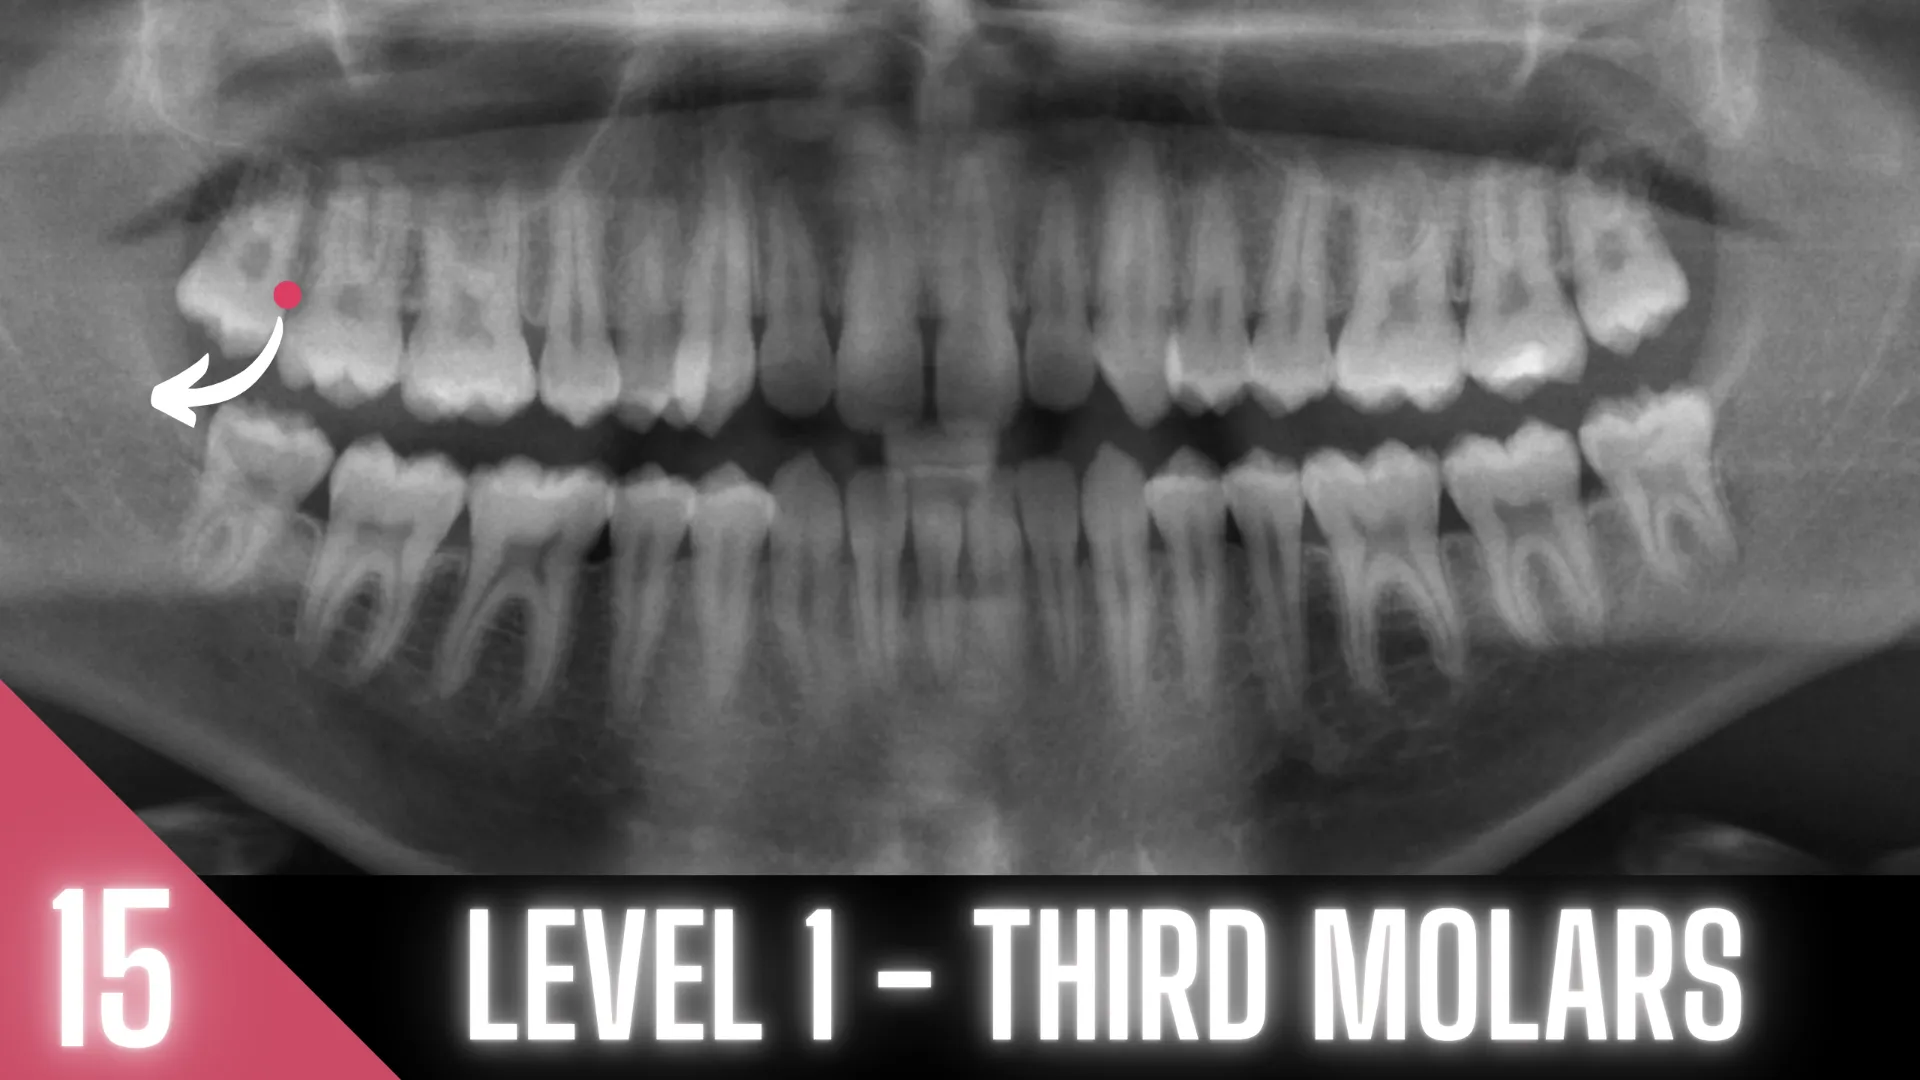

MODULE 15: THIRD MOLARS

Level 1 Case Studies

These radiographic case studies help you recognize which third molar cases are appropriate when you’re confident with extractions but new to wisdom teeth. Case selection is crucial—an oral surgeon once told me he loves driving fast, but that doesn’t make him a race car driver!  This module keeps you within safe limits while you progress to tougher cases.

• Identify radiographic indicators of simpler vs. more difficult third molar cases.